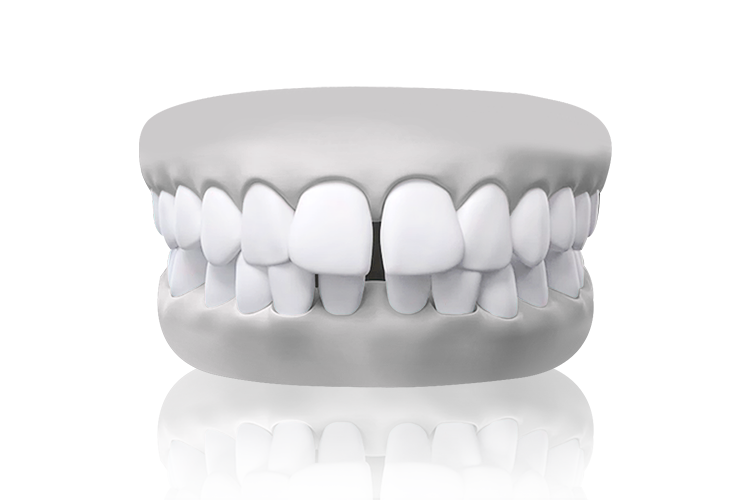

Crossbite teeth model – misalignment of dental arches

การสบฟันแบบไขว้ (Scissor Bite)

การแก้ไขฟันสบไขว้ เพื่อการสบฟันที่สมมาตร

ฟันสบไขว้คือภาวะที่ฟันบนหนึ่งซี่หรือมากกว่าสบอยู่ด้านในของฟันล่าง ซึ่งอาจทำให้เกิดการสึกของฟันอย่างไม่เท่ากันหรือปัญหาข้อต่อขากรรไกร การจัดฟันช่วยปรับแนวการสบฟันให้ถูกต้อง เพื่อประสิทธิภาพในการใช้งานที่ดีขึ้นและความสมดุลของใบหน้า

ตัวอย่างในชีวิตจริง